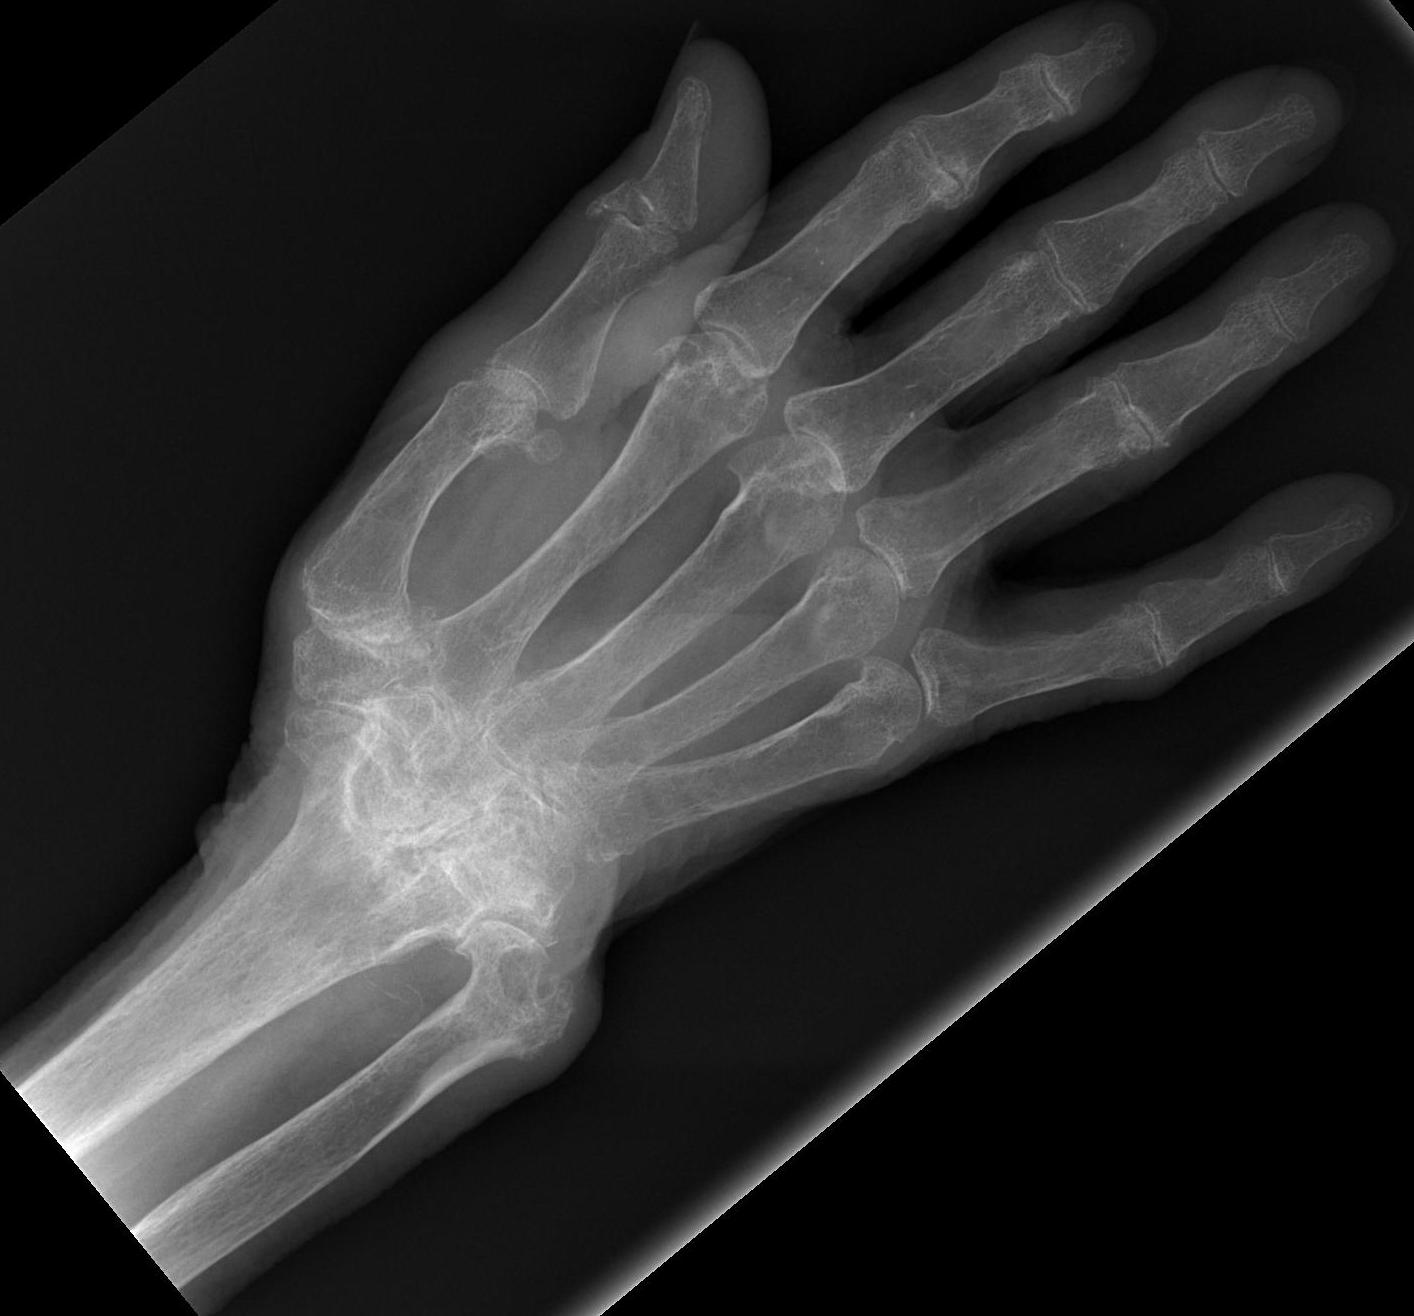

Rheumatoid Wrist

Epidemiology

Extremely common

- 90% by 10 years have wrist problems

Principles

Landsmeer 1961

- treat wrist at same time as treat fingers or will recur

Frequently combine procedures

- synovectomy

- tendon transfer

- ulna procedure

Rheumatoid Arthritis